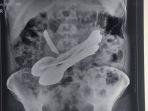

dokter menemukan sendok baja kecil

Pria ini memakan barang-barang tak lazim. Di dalam perutnya, ada tujuh sendok baja kecil, dua sikat gigi, dua obeng kecil, sebilah pisau, dan tongkat.